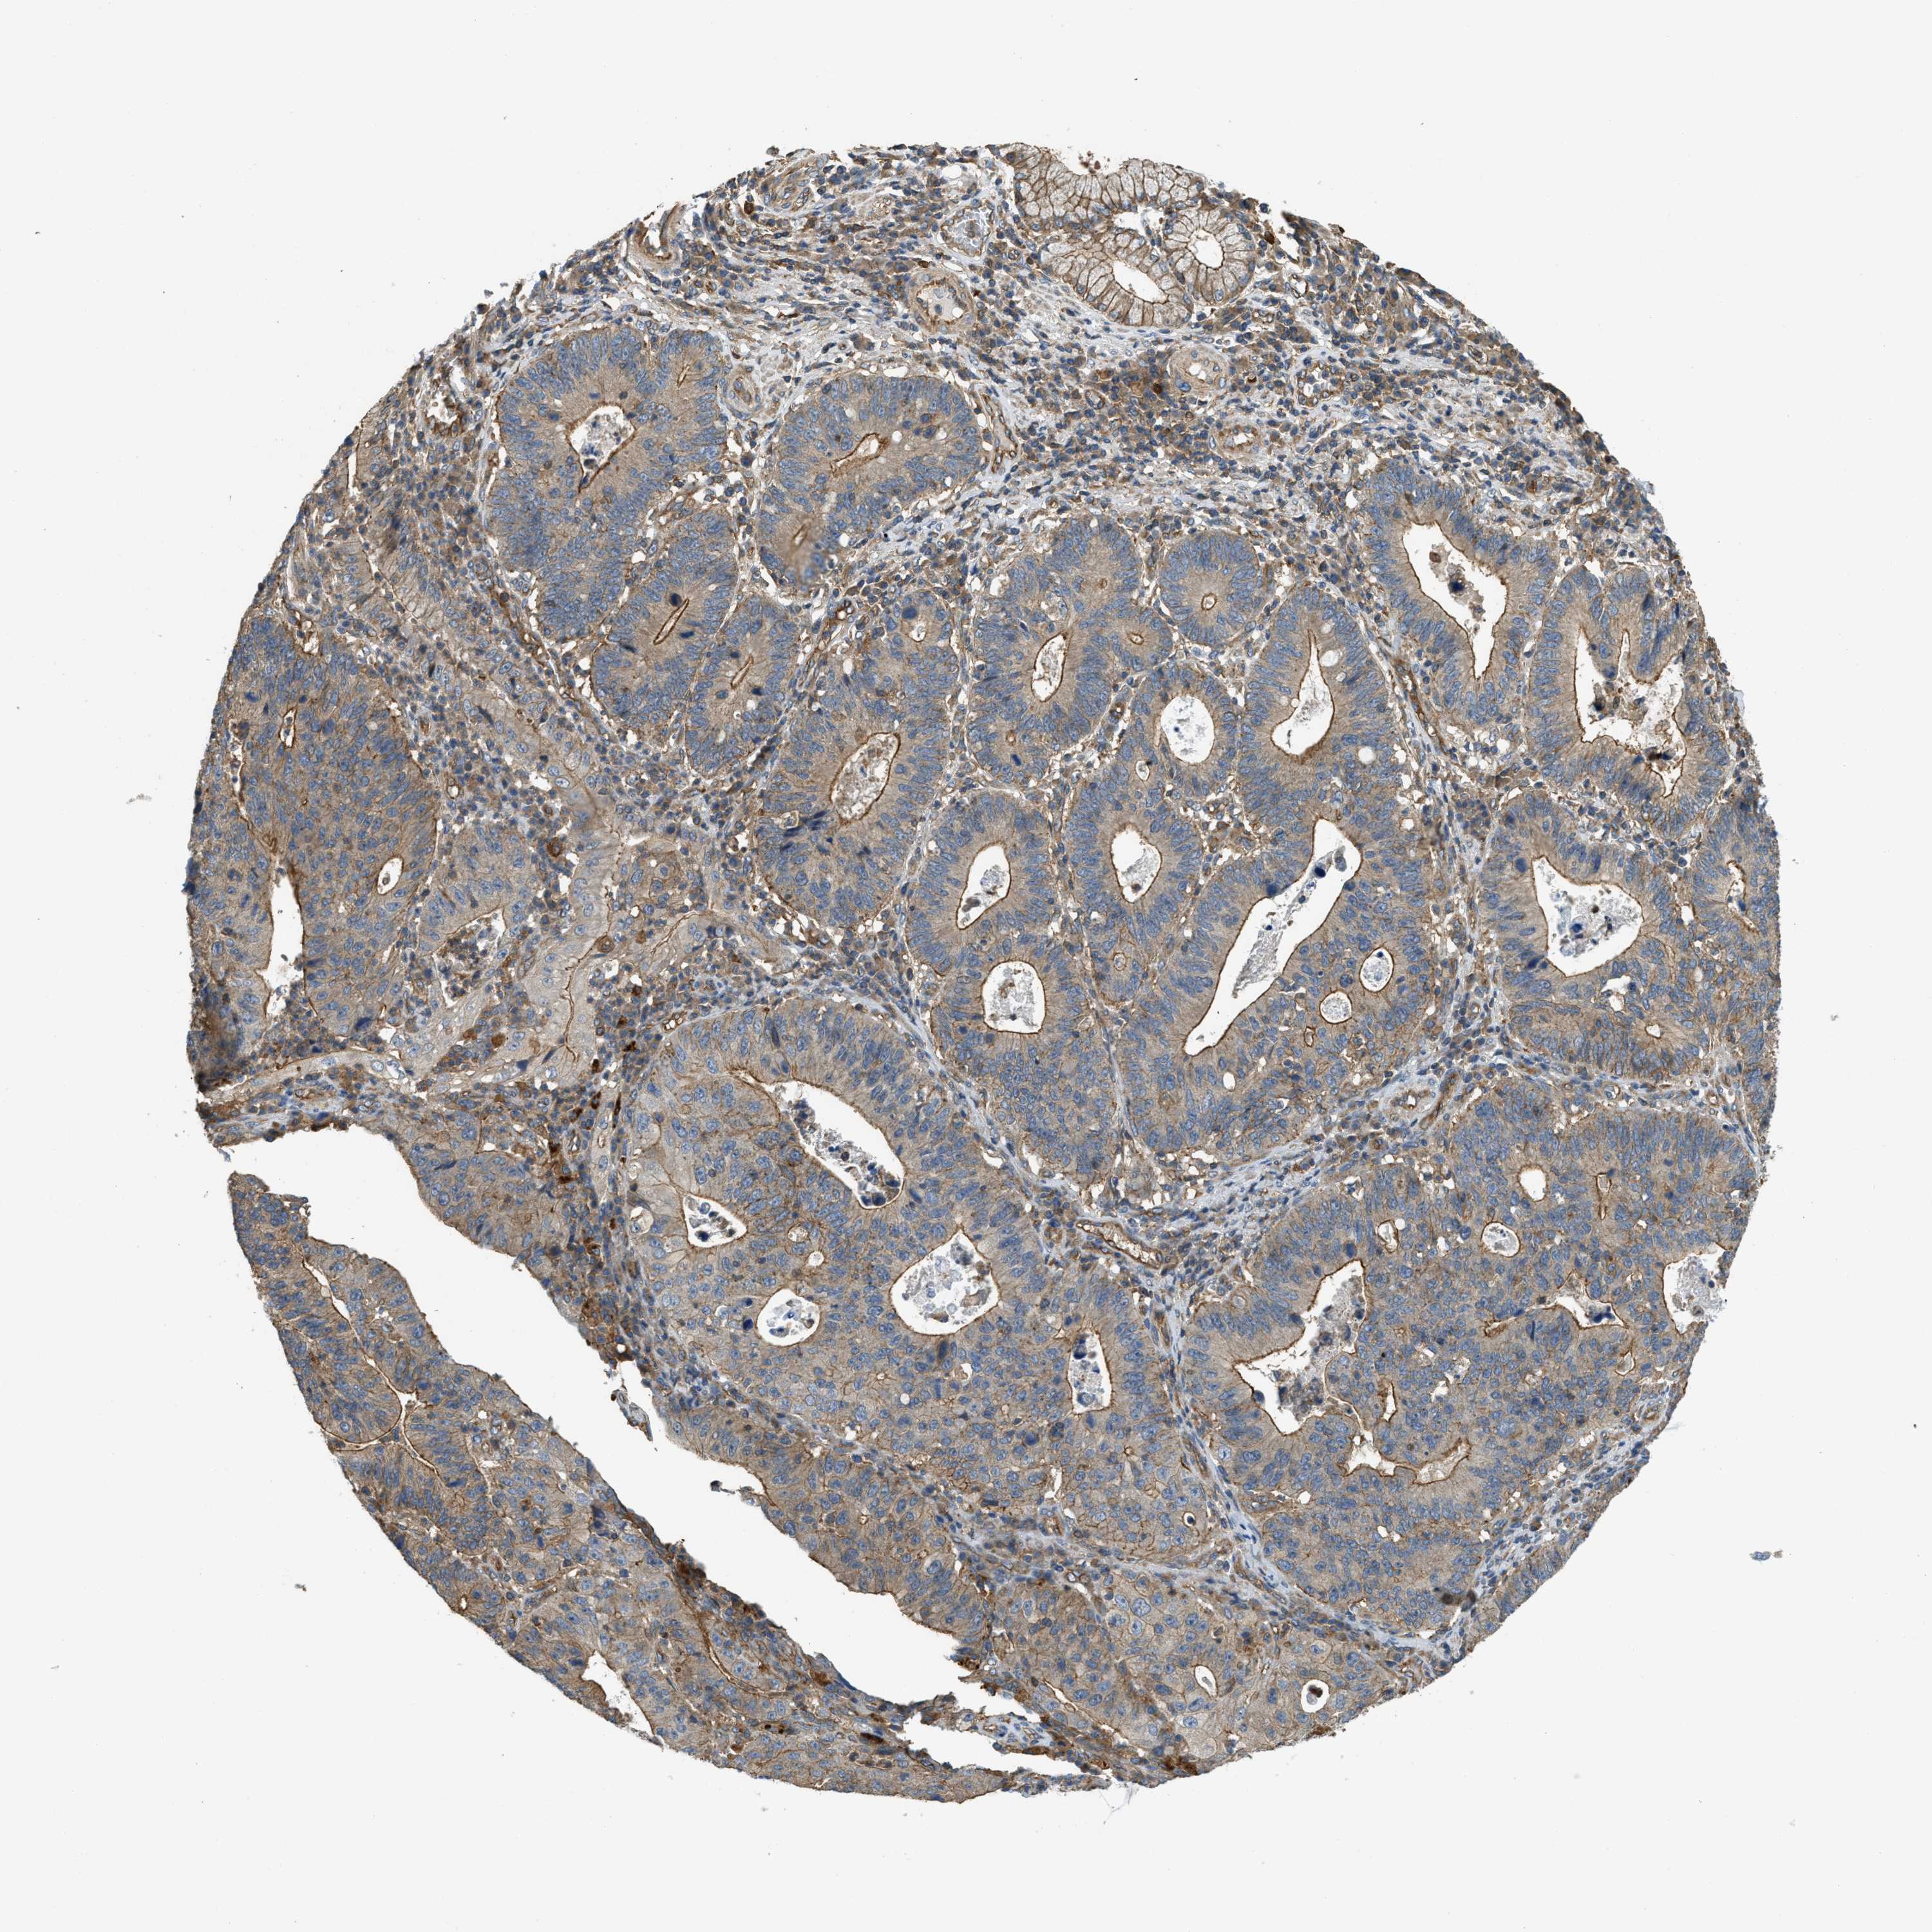

STOMACH CANCER - Protein expressioni

A mouse-over function shows sample information and annotation data. Click on an image to view it in a full screen mode. Samples can be filtered based on level of antibody staining by selecting one or several of the following categories: high, medium, low and not detected. The assay and annotation is described here.

Note that samples used for immunohistochemistry by the Human Protein Atlas do not correspond to samples in the TCGA dataset.

Antibody stainingi

Antibody staining in the annotated cell types in the current human tissue is reported as not detected, low, medium, or high, based on conventional immunohistochemistry profiling in selected tissues. This score is based on the combination of the staining intensity and fraction of stained cells.

Each image is clickable and will lead to virtual microscopy that enables deeper exploration of all samples and also displays staining intensity scores, fraction scores and subcellular localization as well as patient and tissue information for each sample.

Antibody HPA018951

Antibody CAB013716

Staining

High

Medium

Low

Not detected

Intensity

Strong

Moderate

Weak

Negative

Quantity

>75%

75%-25%

<25%

None

Location

Nuclear

Cytoplasmic/membranous

Cytoplasmic/membranous,nuclear

Adenocarcinoma, NOS

Adenocarcinoma, High grade